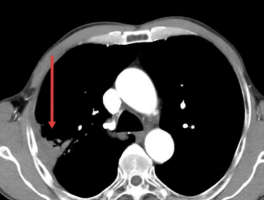

经过2周期的精准化疗,2025年8月26日,李大爷复查CT结果显示肺部肿瘤已缩小至4.3cm×2.3cm,疗效评估达到部分缓解(PR)。这一显著的“降期”效果,为李大爷赢得了宝贵的手术机会。“这个结果令人振奋。”主管医师严双丽表示,“通过我们精准的化疗方案,不仅有效控制了肿瘤进展,更重要的是实现了临床降期,为患者创造了根治性手术的条件。这充分体现了肿瘤内科在转化治疗中的关键作用。”

2025-8-26,肿瘤明显缩小